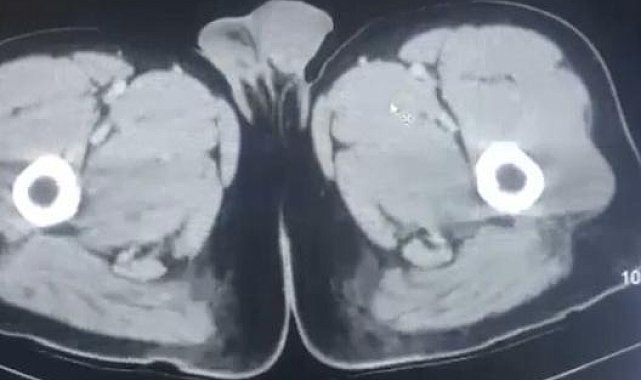

KAYSERİ'de, polisin uyuşturucu operasyonunda yakalanan İran uyruklu 3 şüphelinin midelerinden kapsül halinde toplam 212,8 gram uyuşturucu çıktı. Şüpheliler çıkarıldıkları mahkemece tutuklandı.İl Emniyet Müdürlüğü Narkotik Suçlarla Mücadele Şube Müdürlüğü ekipleri, İran uyruklu R.M.B. (29), S.N.A. (28) ve R.Y.A.'nın (27) yurt dışından kente uyuşturucu getireceği bilgisine ulaştı. Şüpheliler düzenlenen operasyonla gözaltına alındı. 3 şüpheli muayene olmak üzere Kayseri Şehir Hastanesi'ne getirildi. Röntgen ve ultrason sonrası kontrollerde 3 şüphelinin midesinde uyuşturucu madde olduğu belirlendi. Şüphelilerin yaklaşık 17 kapsül halinde 212,8 gram uyuşturucu yuttuğu tespit edildi. Kapsüller, sağlık ekibinin müdahalesiyle çıkarıldı. Taburcu edilen şüpheliler, emniyetteki işlemlerinin ardından çıkarıldıkları mahkemece tutuklandı.